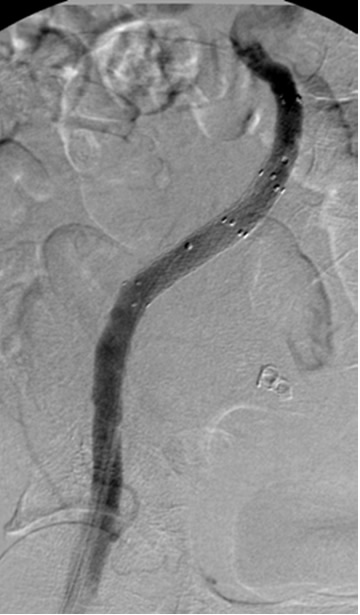

- Simple iliac TASC type A lesions are treated with balloon angioplasty using .035-inch compatible angioplasty balloons with diameters of 5-10 mm and lengths between 20-40 mm. In distal aortic or bifurcation disease, a kissing balloon approach may be necessary (Figure 1). Indications for stenting include suboptimal results of angioplasty with residual gradients, extensive dissection, total occlusion, reoccurrence after angioplasty, ostial location, severe calcification as well as aneurysms. Most commonly balloon expandable stents are used that offer greater radial force, and greater precision for placement for ostial and calcified lesions. More flexible self-expanding stents offer better taper for longer lesions, and are used for antegrade approach, treatment of external iliac and common femoral lesions, and longer lesions. Finally stent grafts are commonly used for aneurysmal pathologies or vascular ruptures.

![]() |

| Figure 1: Kissing balloon for proximal common iliac disease. |